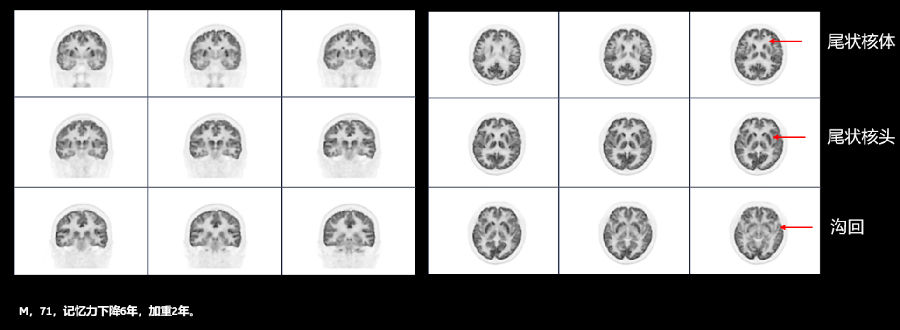

4、神经系统疾病的诊断

PET/CT对脑血管疾病、血管性疾病引起的功能性改变、阿尔兹海默症、癫痫的定位、脑肿瘤定性 和复发判断、帕金森病的早期诊断等有独到的优势。